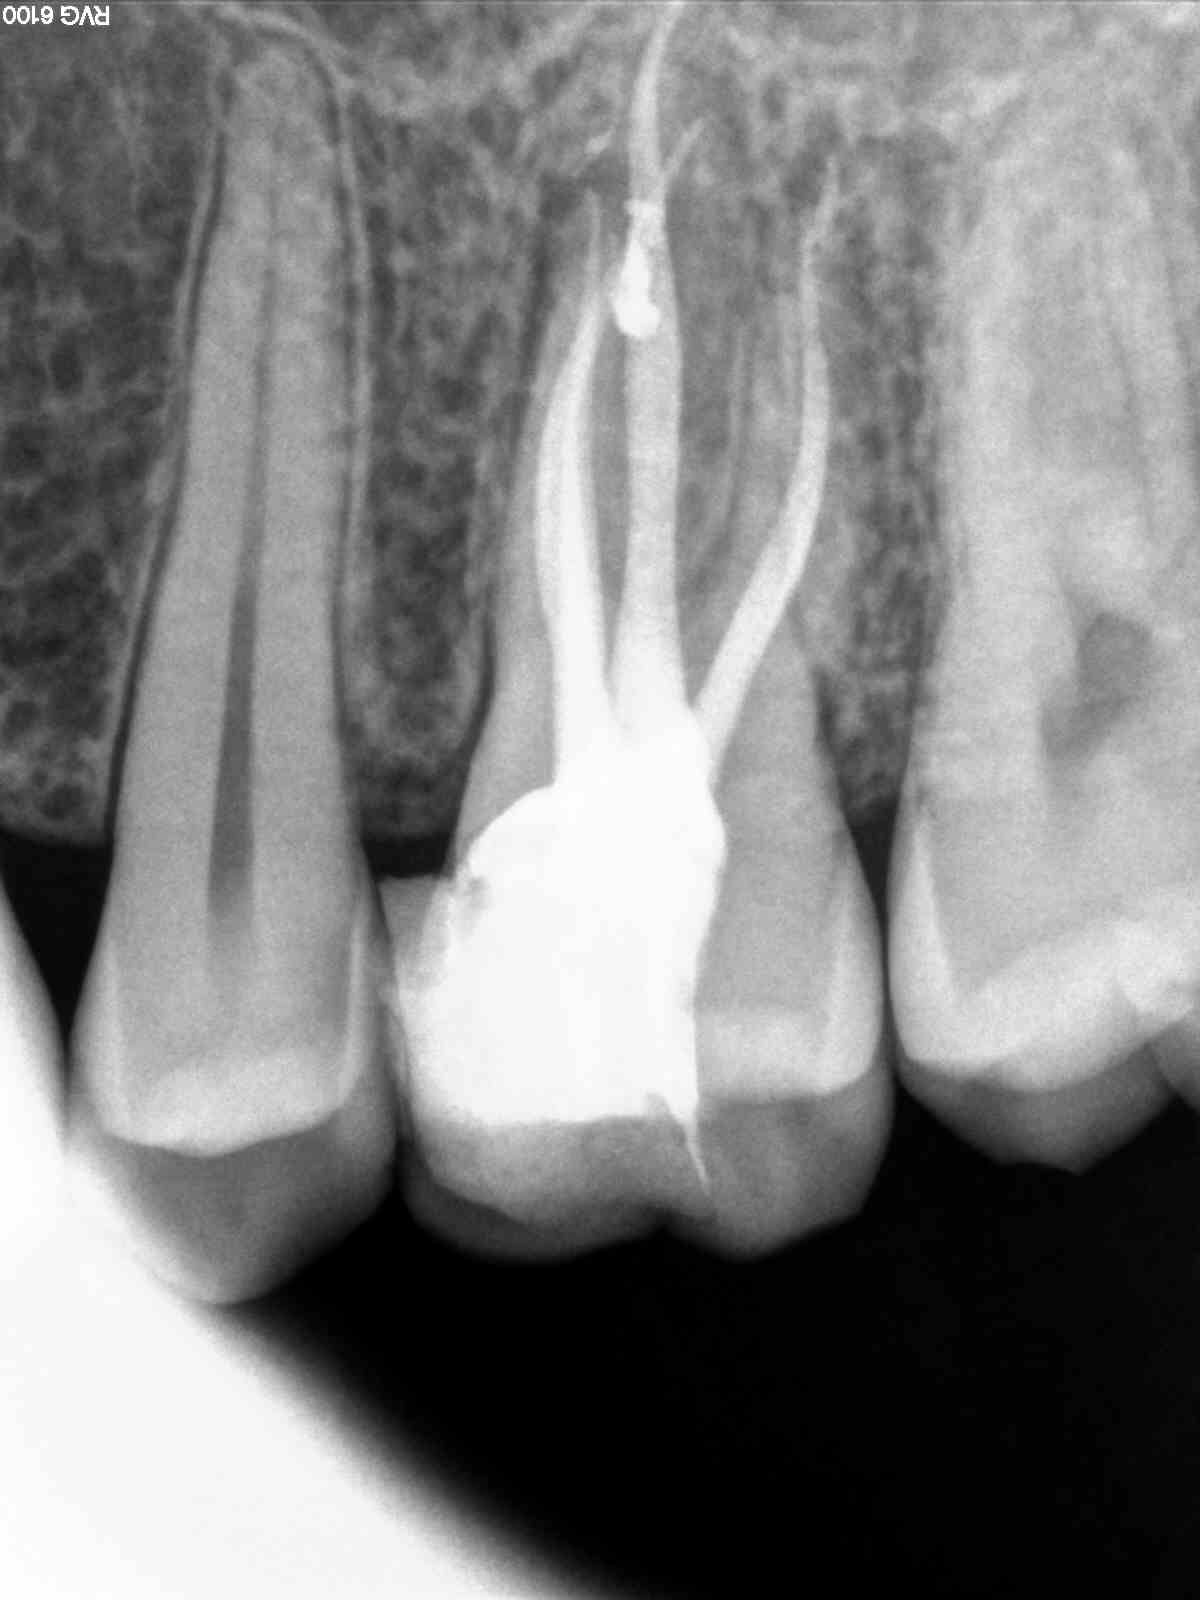

Bon, ça me fatigue ce capteur, je ne sais plus interpréter mes Rx ...

Sérieusement vous voyez quelque chose sur le deuxième cliché ?

Le premier pris il y a 2 mois, lors de l'endo avec le trophy, et le deuxième cliché avec le kodak, je n'arrive pas à dire si c'est en voie de guérison :((

Même avec le filtre de netteté, en bidouillant les contrastes, j'y vois quedal :(